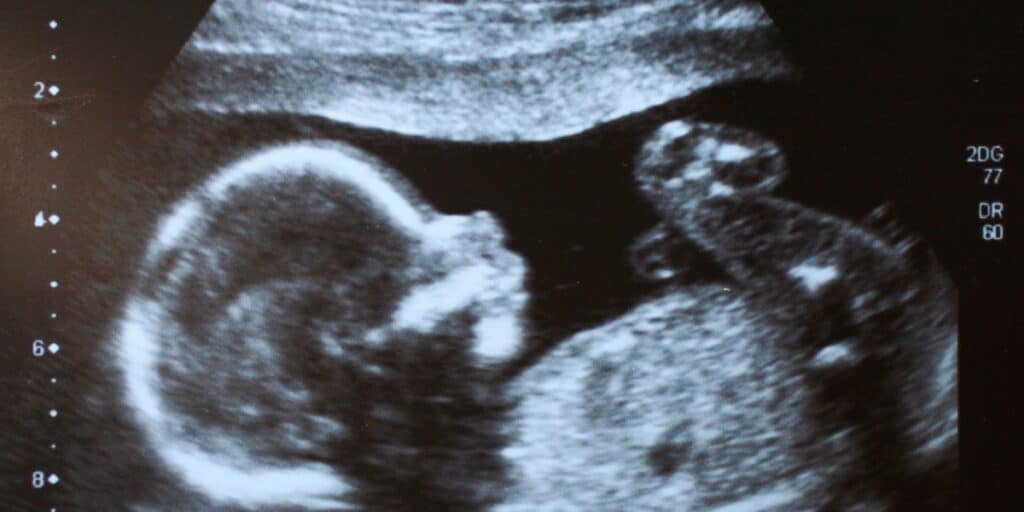

O avanço tecnológico permitiu facilitar, e muito, diversos processos, inclusive a gestação. A ultrassonografia tornou-se uma ferramenta indispensável no acompanhamento pré-natal, permitindo a visualização detalhada do desenvolvimento fetal em diferentes fases da gravidez.

Esse exame é fundamental para avaliar a saúde do bebê, identificar precocemente possíveis anomalias e fornecer informações importantes para a equipe médica. Além do aspecto clínico, a ultrassonografia também proporciona um momento especial para os pais, que podem acompanhar de perto o crescimento do bebê e fortalecer o vínculo afetivo antes mesmo do nascimento.

Com diferentes tipos de ultrassonografia disponíveis, cada um com sua finalidade específica, esse exame se consolidou como um dos principais aliados para uma gestação mais segura e tranquila.

A ultrassonografia desempenha um papel essencial no acompanhamento da gestação, garantindo mais segurança tanto para a mãe quanto para o bebê. Esse exame permite avaliar o desenvolvimento fetal em cada trimestre, identificando possíveis anomalias estruturais ou funcionais e auxiliando na detecção precoce de complicações que podem exigir intervenções médicas.

Além disso, a ultrassonografia é uma ferramenta indispensável para monitorar a placenta, o líquido amniótico e a posição fetal, informações que são fundamentais para a condução do parto. O exame também possibilita o acompanhamento de doenças maternas pré-existentes ou que possam surgir durante a gravidez, permitindo um planejamento mais adequado dos cuidados necessários.

Por ser parte integrante do pré-natal, a realização da ultrassonografia contribui para uma gestação mais segura, promovendo um acompanhamento detalhado e personalizado conforme as necessidades de cada gestante.